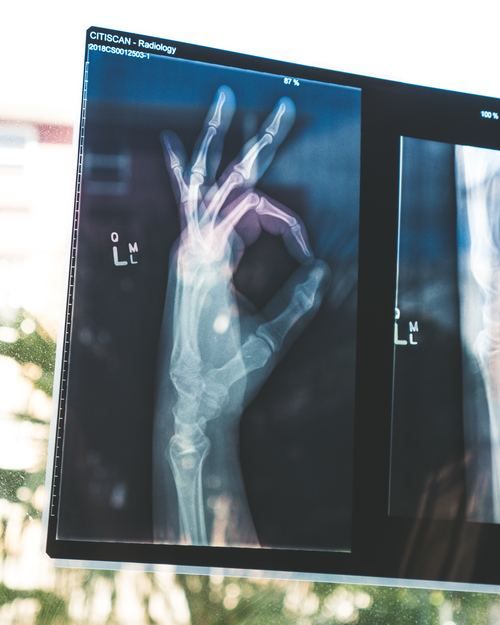

Photo by Owen Beard on Unsplash

Osteoporosis is a disorder of the bones characterized by decreased bone strength predisposing to an increased risk of broken bones.